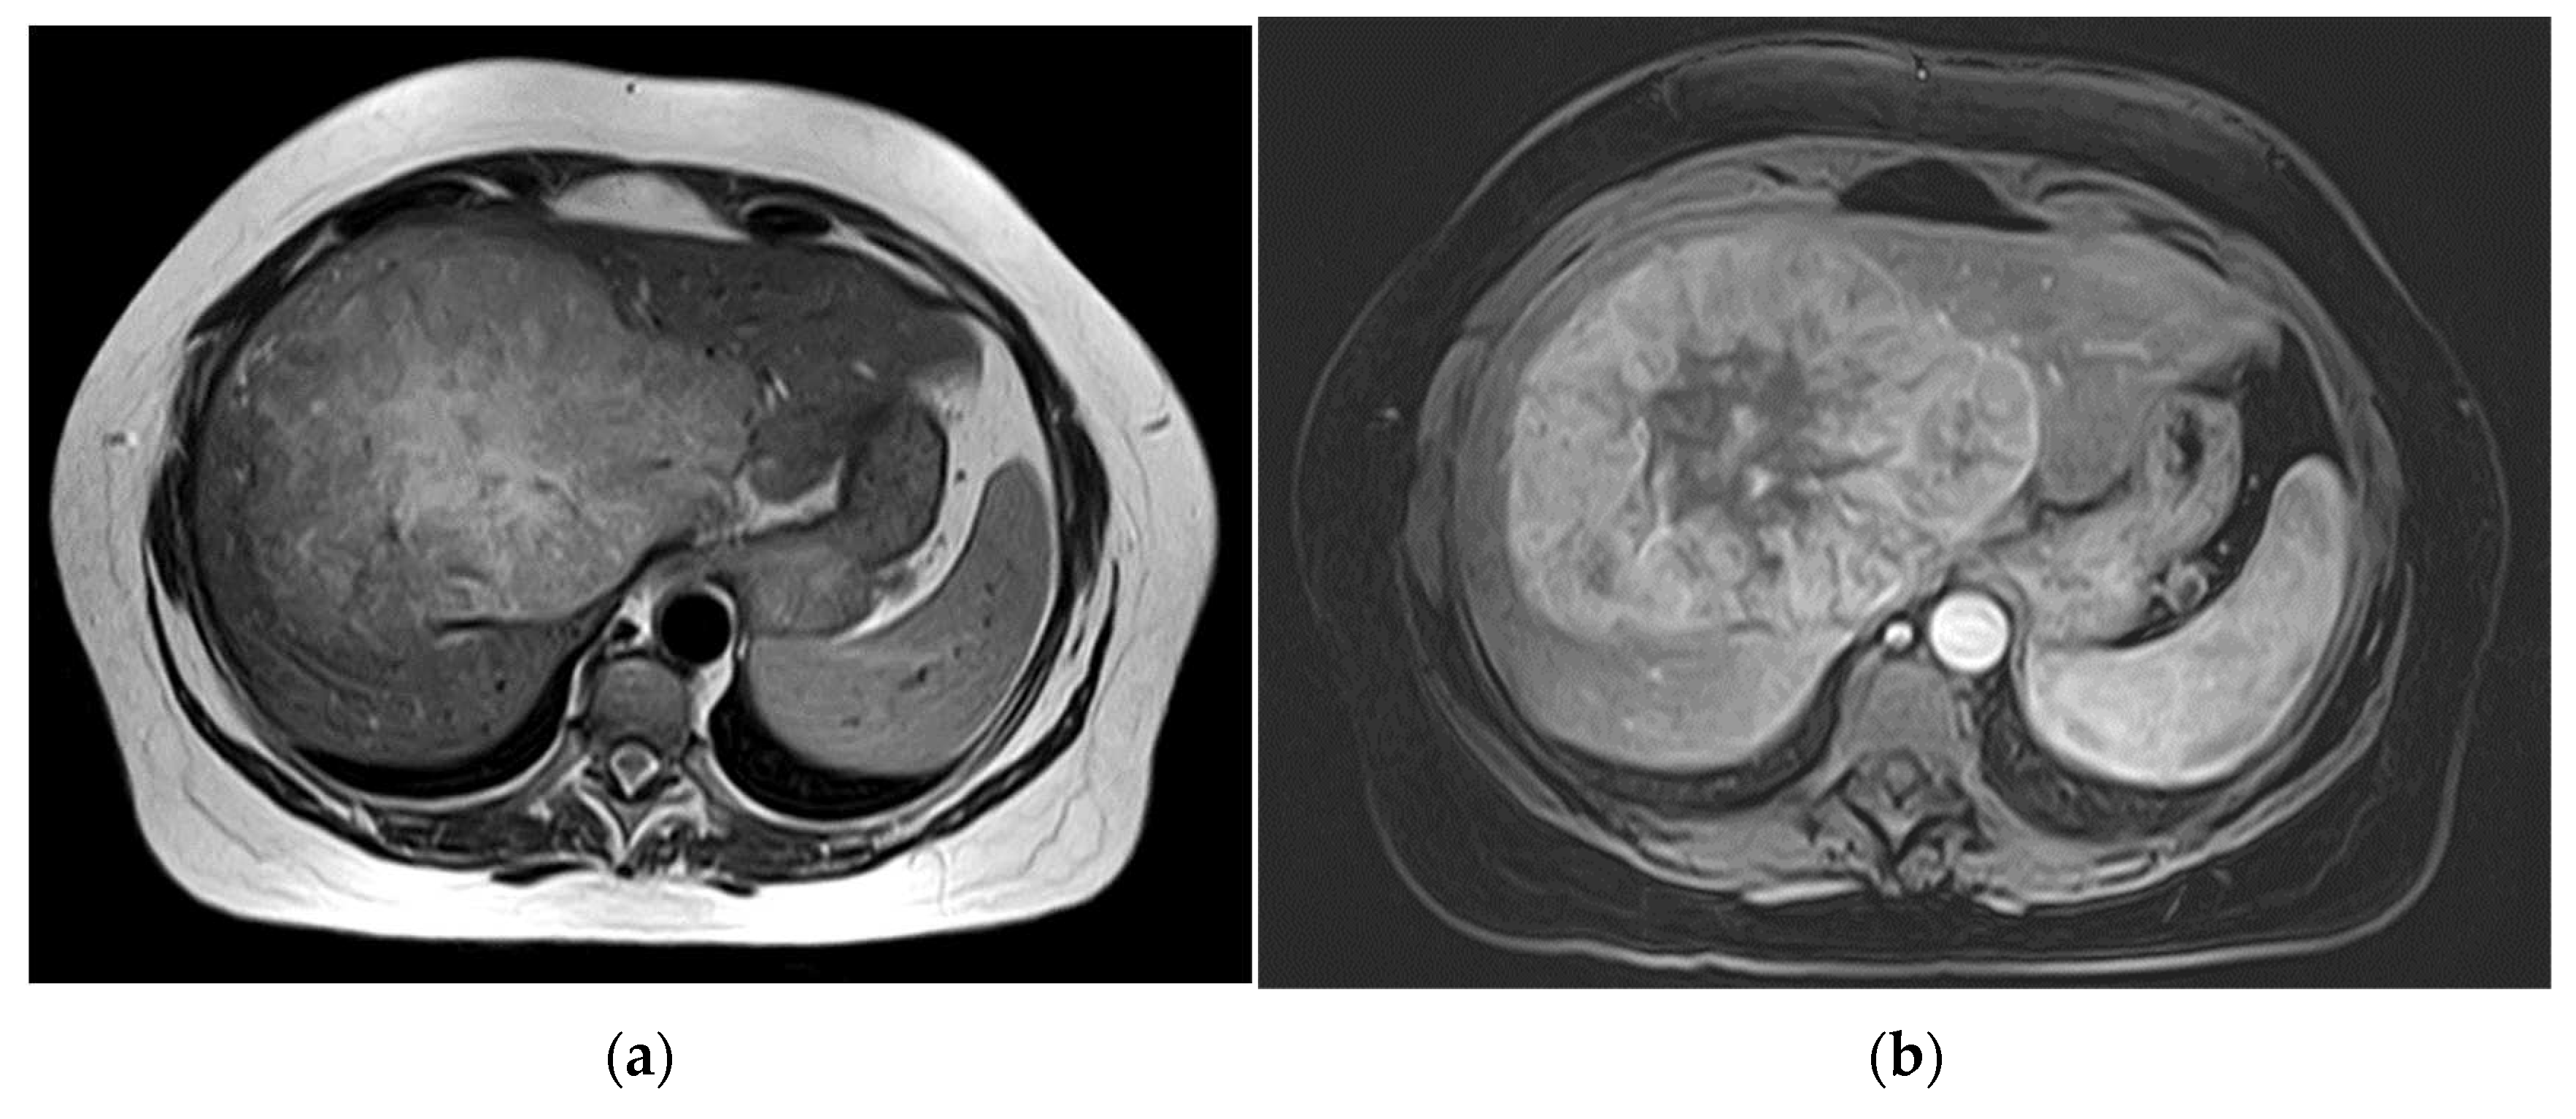

Figure 2. Pre-operative MR imaging Patient 2: (a) Arterial phase imaging depicting hyperenhancement of liver lesion; (b) T1 sequence with fat saturation in hepatobiliary phase depicting isointensity to liver; (c,d) T1 sequence with fat saturation post contrast showing size progression from (c,d) in 3 years.

The second patient was referred to our out-patient clinic with a liver lesion of the left lobe, which had been growing constantly over 7 years. A FNH had been diagnosed at the age of 23, which met the typical MRI-criteria including contrast retention in hepatobiliary imaging and the patient was in regular follow-ups (Figure 2). Because of the tumor growth and inhomogeneity along the tumor capsule we performed a left hepatectomy (H234′) (Figure 2d). The final histological findings revealed a HCC and the patient is in regular follow-ups since without evidence of recurrence for over 44 months until today.